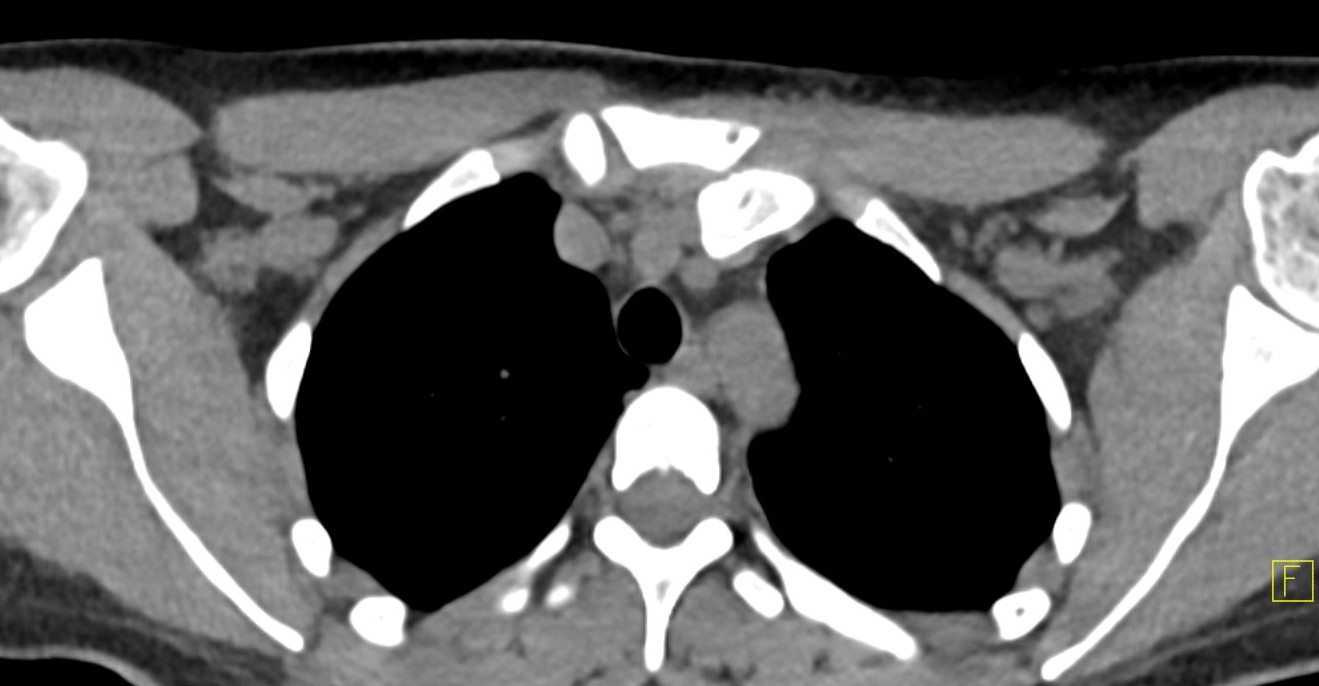

CT scan

Left posterior SCJ dislocation with pre- and post angiogram

Severe left posterior SCJ dislocation with subclavian vein compression